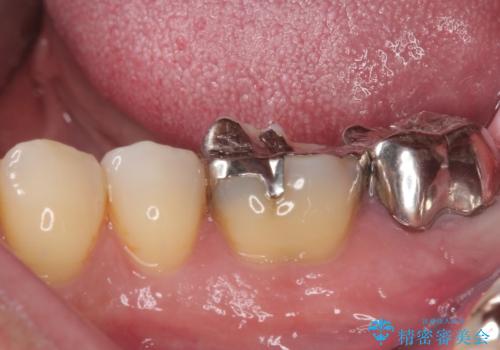

- 奥の銀歯が外れしまったとのことで来院された患者様です。

非常に咬合力が強く、銀歯の周りの歯がむし歯になっている状態でした。

部分的な詰め物ですと、再度周辺がむし歯になるリスクが高いと考えられたため、オールセラミッククラウンにて補綴治療を行うこととしました。